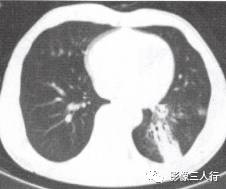

胸部CT图像显示,在含气少的致密肺的背景上见到含气的支气管,表现为两种形态: ①在大片肺实变病灶内的细条状空气密度影;②直径Imm的小泡状空气密度影,连续的几 个层面都能出现(图2、图3)。该征象表明:①近侧气道通畅;②肺泡内的空气经吸收(肺不张)或取代(肺炎、肺癌),或两者综合而消失。通畅含气的支气管在肺泡实变高 密度区内表现为管腔内低密度充气轮廓。 医学百科网 | YxBaike.Com